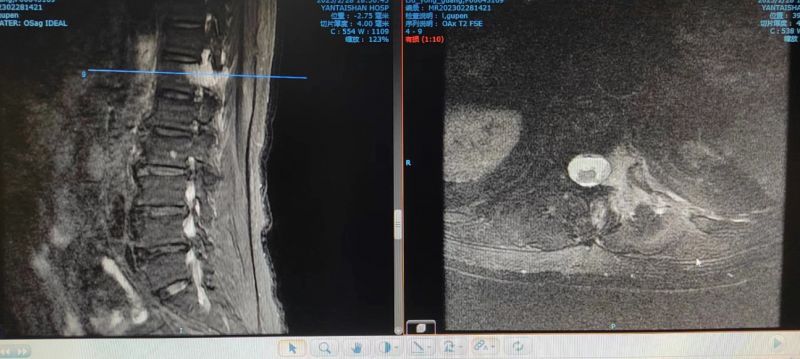

73岁的刘大爷是一位肺癌患者,自从去年11月查出肺部肿瘤之后一直坚持治疗,精神状态及生活质量均与常人无异。然而就在1个月前,他开始感到左侧睾丸疼痛,并且伴有左下腹部的撕扯放射痛,服用强效止痛药,疼痛非但没有缓解,反而逐日加重,以至于彻夜难眠,严重影响着他的生活质量。刘大爷不得已来到医院,在接受相关检查后发现多发脏器转移灶,但没有找到疼痛直接原因。转到疼痛科后,通过胸腰段磁共振检查找到了疼痛的罪魁祸首,原来是刘大爷体内的肿瘤进展并出现了第十二胸椎左侧横突部的转移。

通过胸腰段磁共振检查,找到引发患者痛疼的原因。

科室经过讨论,考虑T12的转移灶及局部水肿可刺激同侧椎管内下行的神经根,支配睾丸及阴囊的神经为生殖股神经生殖支,起源于腰1、2神经分支,分别从L1.2和L2.3椎间孔发出汇成生殖股神经,与患者左下腹部、腹股沟及阴囊的疼痛相吻合。